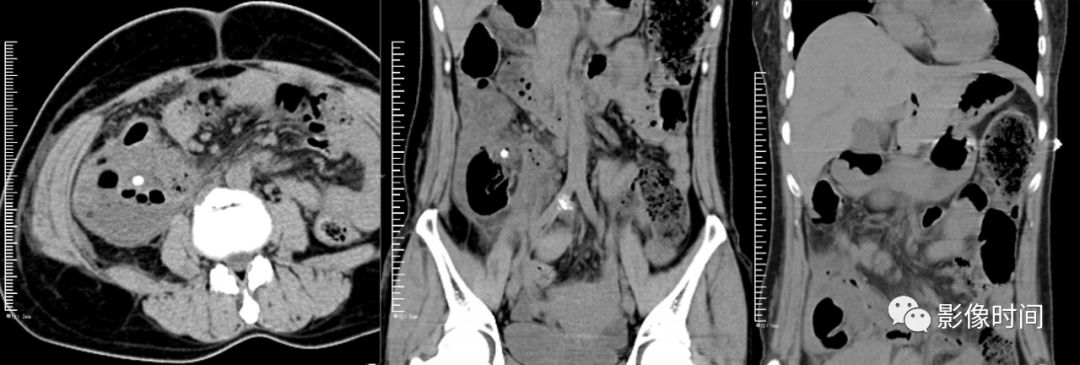

小心误诊,这可不是急性阑尾炎!

盲肠憩室内环形粪干(红箭),憩室周围无渗出;盲肠憩室内结节状粪石

炎伴阑尾周围炎;若阑尾无显示,但阑尾区有粪石出现且伴有盲肠周围炎